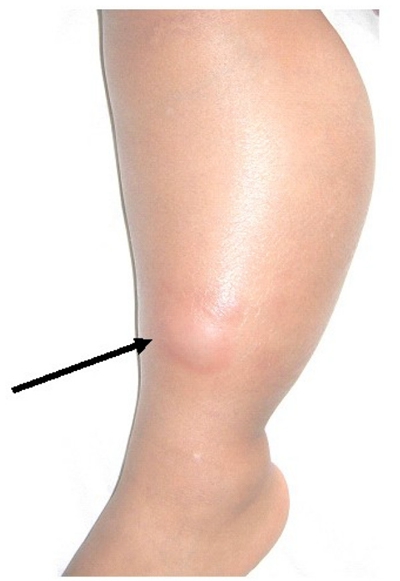

骨癌圖片

骨癌